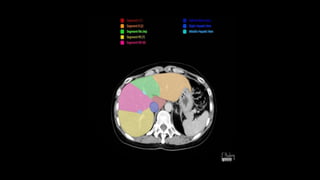

SEGMENTAL ANATOMY OF LIVER

• The French surgeon and anatomist Claude Couinaud divided the liver

into eight functionally independent segments

• allows resection of segments without damaging other segments.

• Each segment has its own vascular inflow, outflow and biliary

drainage.

• In the centre of each segment there is a branch of the portal vein,

hepatic artery and bile duct.

• In the periphery of each segment there is vascular outflow through

the hepatic veins.

• Liver is divided into a functional

left and right liver by a main

scissurae containing the middle

hepatic vein.

• This is known as Cantlie's line.

• Cantlie's line runs from the

middle of the gallbladder fossa

anteriorly to the inferior vena

cava posteriorly.

• Right hepatic vein divides the

right lobe into anterior and

posterior segments.

• Left hepatic vein divides the left

lobe into left medial and left

lateral sections.

• The portal vein divides the liver

horizontally into upper and lower

segments.

• There are eight liver segments.

• Segment IV is divided into segment IVa and IVb according to Bismuth.

• The numbering of the segments is in a clockwise manner.

• Segment I (the caudate lobe) is located posteriorly.

• It is not visible on a frontal view.